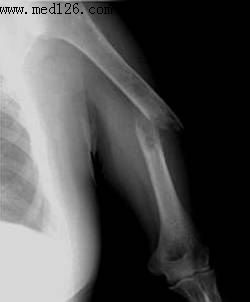

> 正文:左肱骨骨折

左肱骨骨折